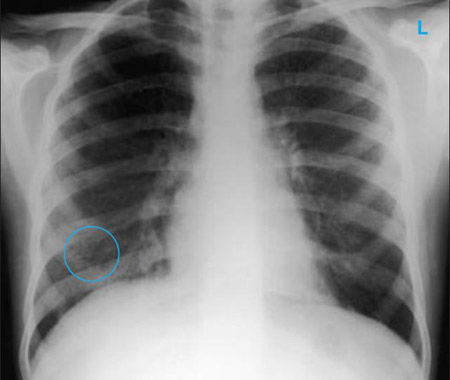

Radiografía de tórax que muestra múltiples nódulos discretos en ambos pulmones (uno de ellos marcado con un círculo) en un paciente con tuberculosis miliar

E. Dick, Student BMJ. 2001;9:10-12